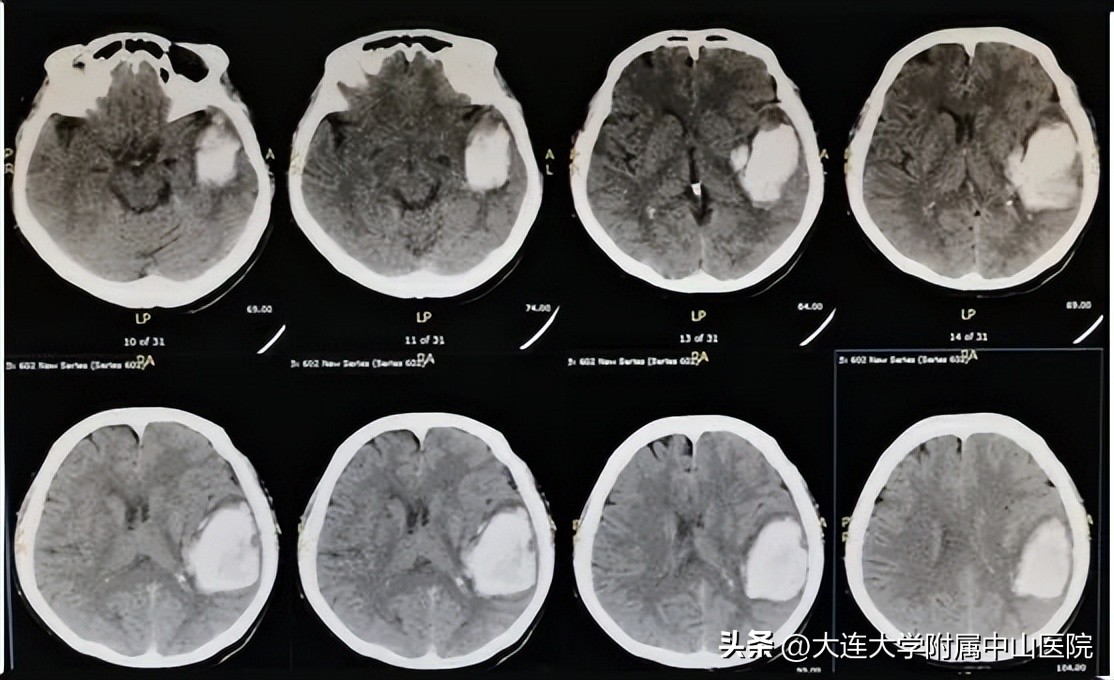

术前CT